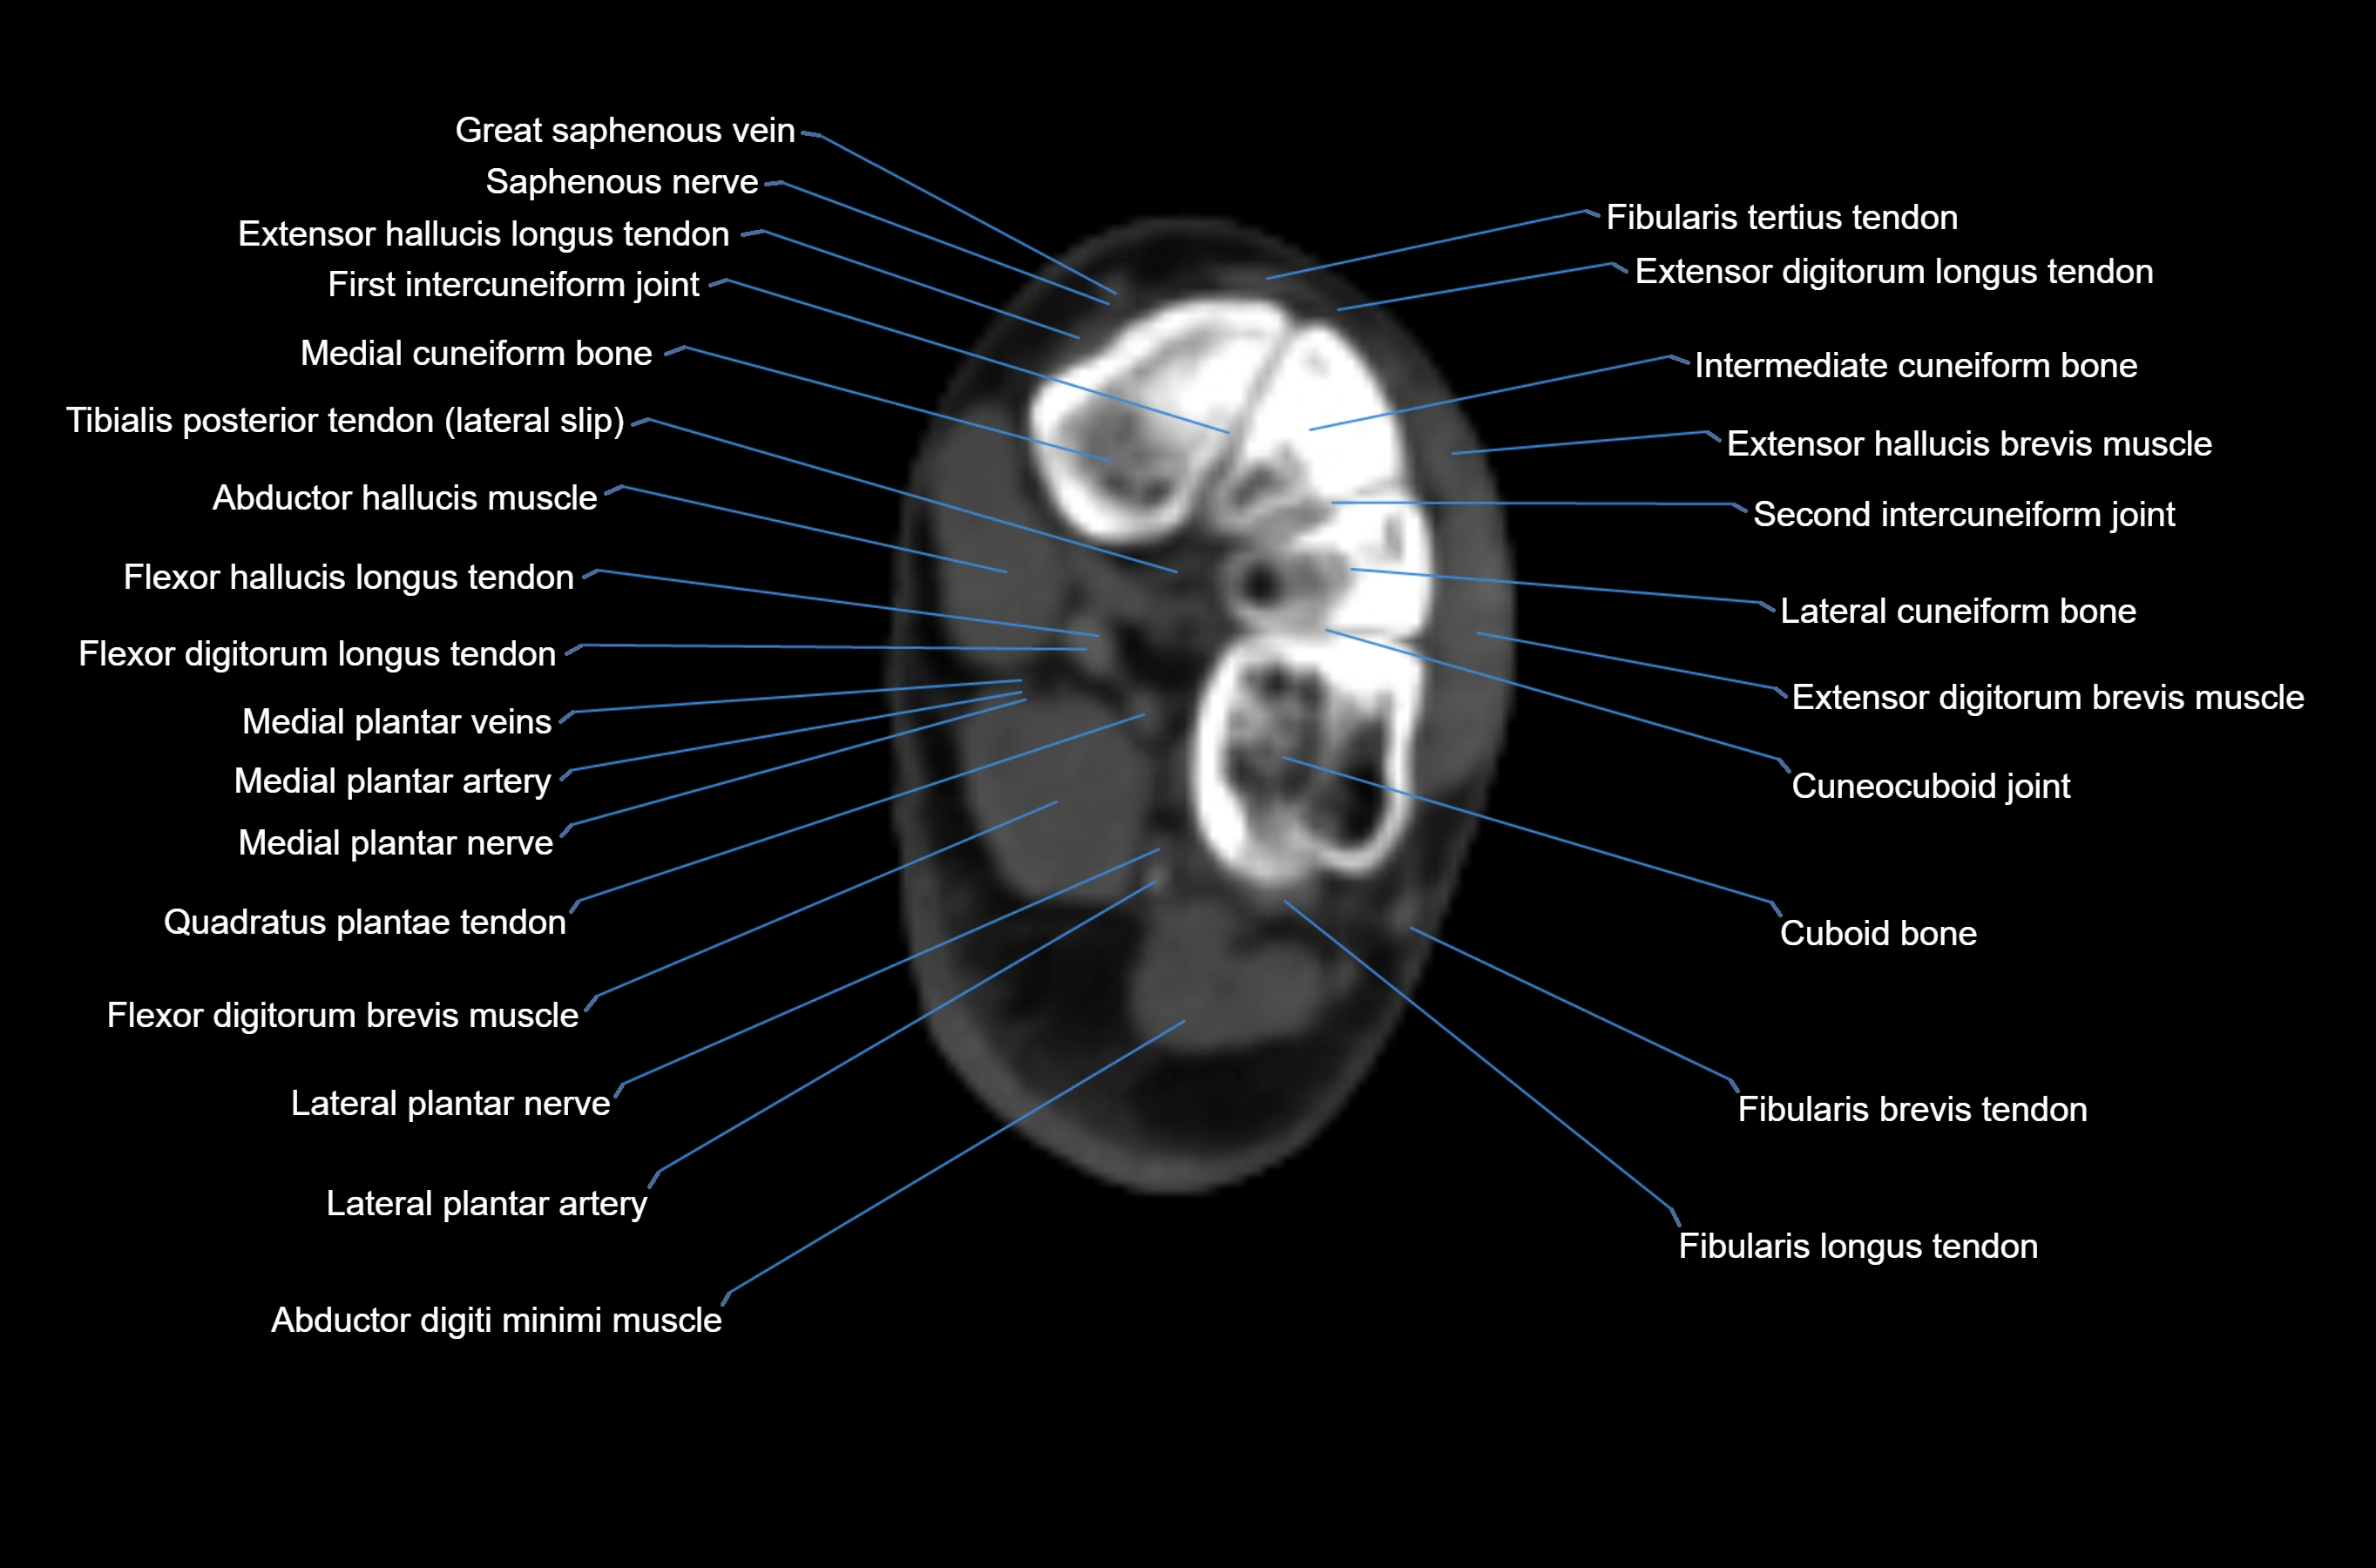

CT image